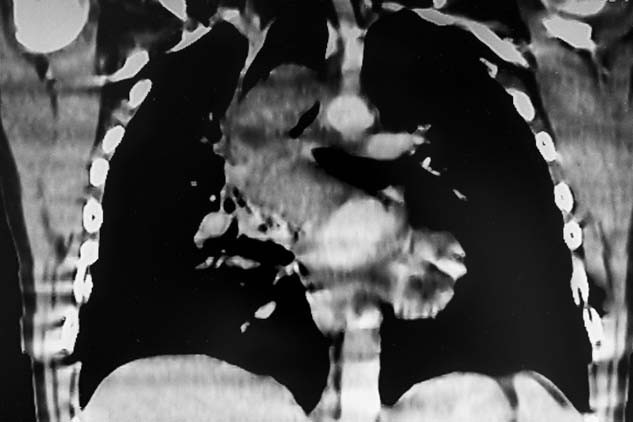

Sekiz saat süren ve oldukça invaziv olan bu ameliyat, vücudunda göğüs kafesinden göbeğinin altına ve sırtına kadar uzanan devasa bir iz bıraktı. İyileşme süreci çok zordu ama yapılan son tomografi taraması, kanserden eser kalmadığını gösterdi.